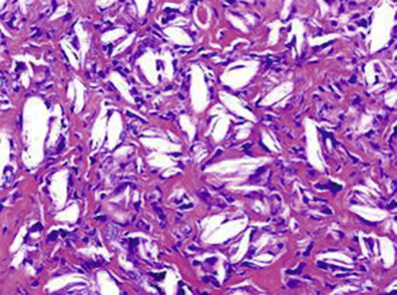

♦ Stippled, not thickened: LCV including IgA vasculitis and HSP

♦ Thickened and smooth: porphyrias with cutaneous involvement and pseudoporphyria; may also see linear BMZ staining in these entities!